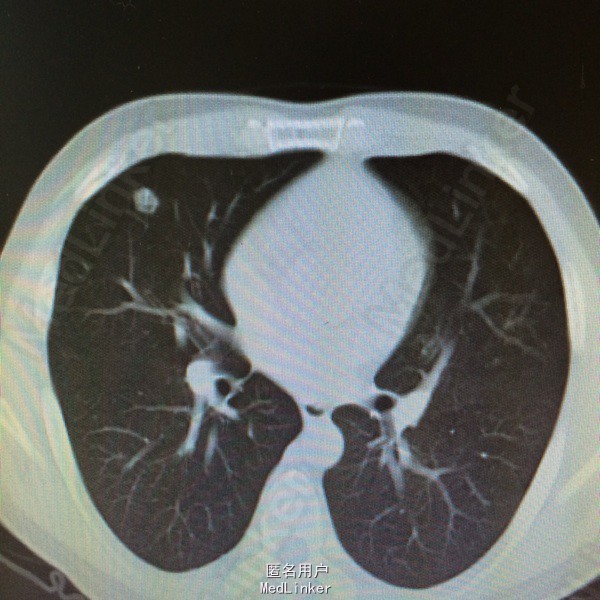

患者因“鼻咽癌放疗后2年余,双肺多发转移治疗后复发2周”入院。详见图片

查体一般可,生命体征平稳,双颈部等浅表未及明显肿大淋巴结,2015.9.15复查ct提示两肺多发转移瘤,较前增多增大。

鼻咽癌肺转移,拟予全身化疗

患者鼻咽癌肺多发转移,目前鼻咽部及双颈部CR,双肺多发转移后予全身化疗及全肺姑息性放疗,放疗后全肺缓解期8个月,未见肺炎。放疗后复发予全身化疗,化疗后缓解期约3个月,现再次复发,但患者血象不宜全身化疗,讨论治疗方案